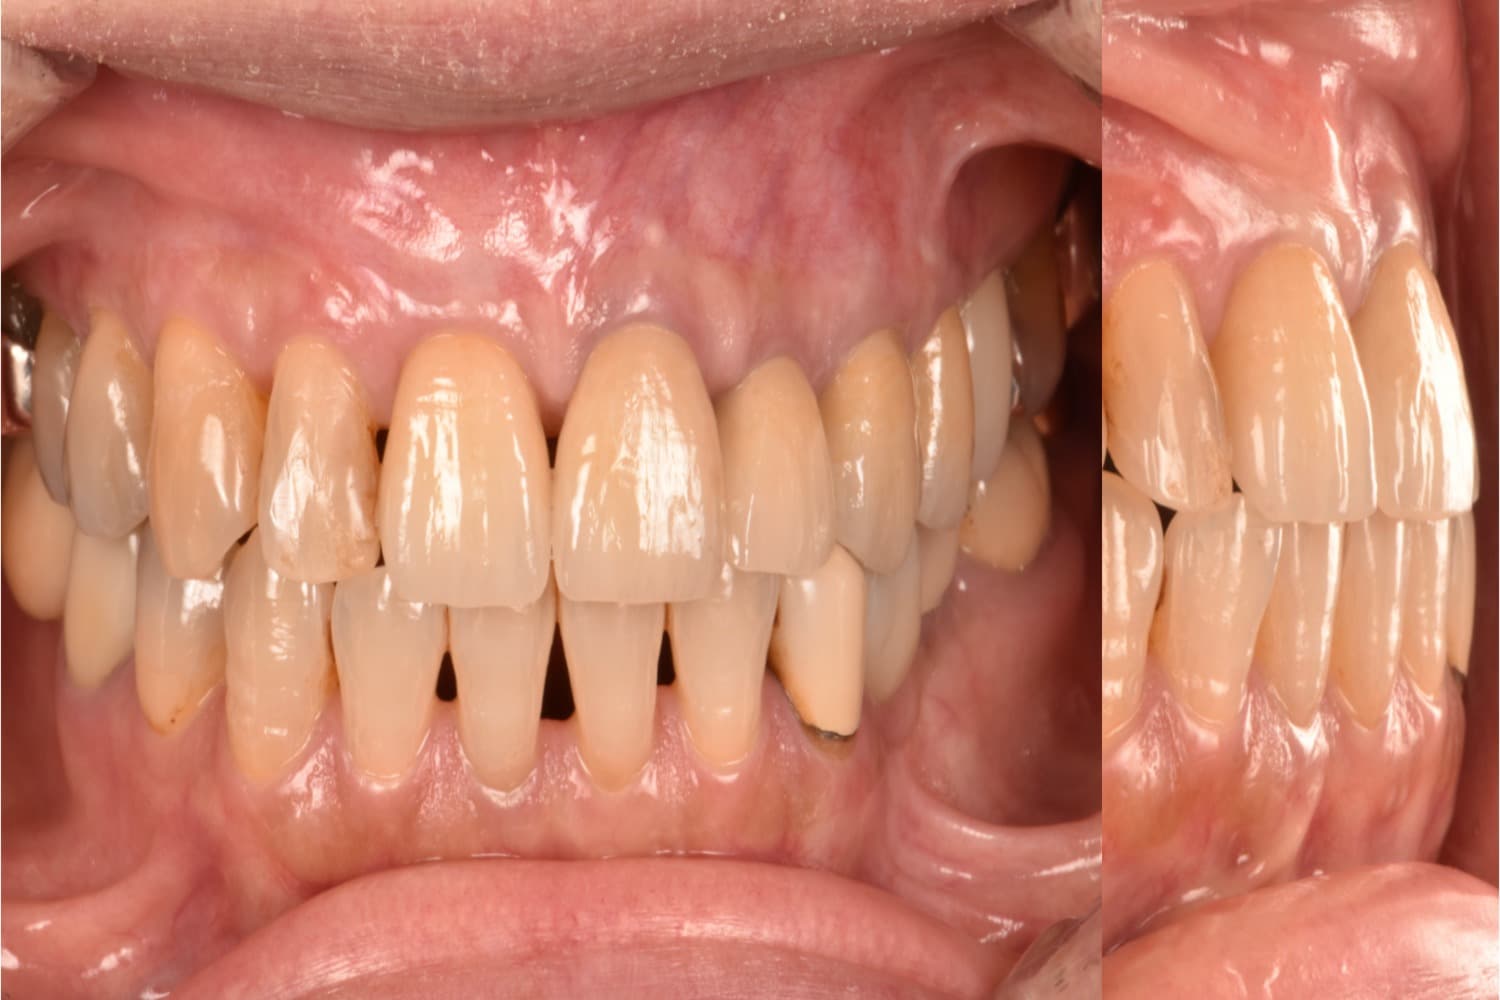

右上1の前歯部のインプラント治療

Before

After

年齢

50代

性別

女性

主訴

前歯を綺麗にしたい

治療期間

10カ月

治療回数

15回

費用

913,000円

副作用・リスク

清掃状態等によりインプラント周囲に炎症を起こす可能性があります。